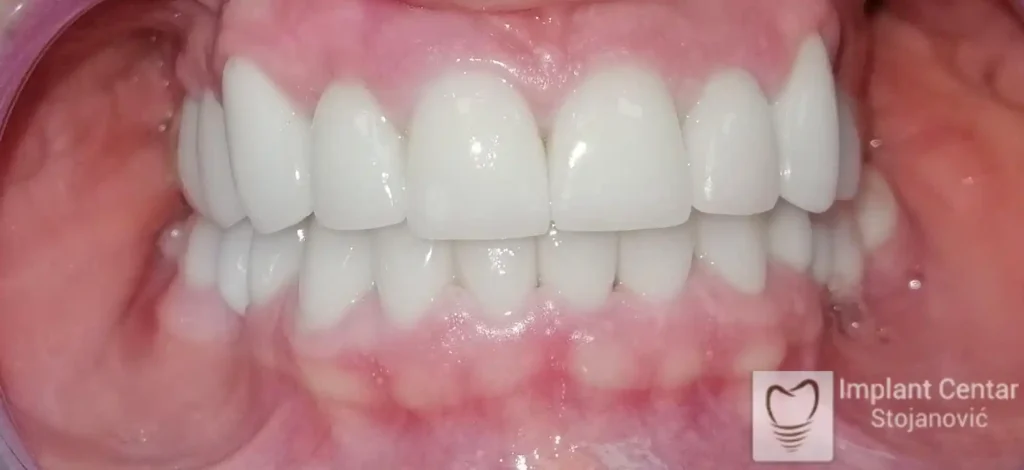

Pacijent sa rascepom usne, nepca i alveolarnog grebena uspešno je rehabilitovan fiksnim protetskim radom na implantatima. Pre dolaska u našu ordinaciju, pacijent je u gornjoj vilici nosio totalnu protezu preko preostalih zuba, dok je u donjoj vilici bio zbrinut parcijalnom mobilnom protezom. Tokom višegodišnje potrage za adekvatnim rešenjem, pacijent nije uspeo da pronađe zadovoljavajuću terapijsku opciju ni u zemlji ni u inostranstvu.

Nakon detaljnog kliničkog pregleda i analize radioloških snimaka, izrađen je sveobuhvatan plan terapije sa ciljem uklanjanja mobilnih proteza i postizanja maksimalne funkcionalne i estetske rehabilitacije. Zbog loše biološke vrednosti preostalih zuba, doneta je odluka o njihovom vađenju i ugradnji dentalnih implantata.

Poseban terapijski izazov predstavljalo je premošćavanje defekta nastalog usled rascepa, kao i ograničena količina raspoložive kosti u gornjoj vilici. Primenom većeg broja implantata i odgovarajućih procedura nadoknade kosti, postignuta je stabilna osnova za fiksni protetski rad.

Tokom perioda oseointegracije, pacijent je bio zbrinut fiksnim privremenim krunicama, čime je već pet dana nakon intervencije obezbeđena potpuna funkcionalna i estetska rehabilitacija. Nakon završetka perioda integracije implantata, izrađeni su definitivni cirkonijum-keramički mostovi na implantatima.

Pacijent je izuzetno zadovoljan postignutim rezultatom, navodeći da po prvi put jasno oseća svoje nepce tokom žvakanja, kao i da se smeje sa punim samopouzdanjem.